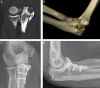

We describe a medial approach to the coronoid where the flexor-pronator mass is released from its humeral origin by creating a proximally based tendinous flap. This technique facilitates access to the coronoid, preservation of the medial collateral ligament origin, and repair of the flexor-pronator mass. This approach has utility for all coronoid fracture variations but especially the O'Driscoll anteromedial subtype 3, which includes fractures of the sublime tubercle, the anteromedial facet, and the coronoid tip.